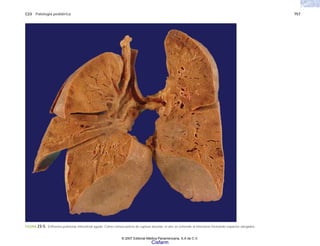

FIGURA 5-4. Asma bronquial. a) Aspecto sobredistendido de los pulmones en un caso fallecido durante un ataque agudo de asma. b) Corte trasnversal de un bronquio en el caso anterior,

que muestra la luz ocupada por material mucoso denso.